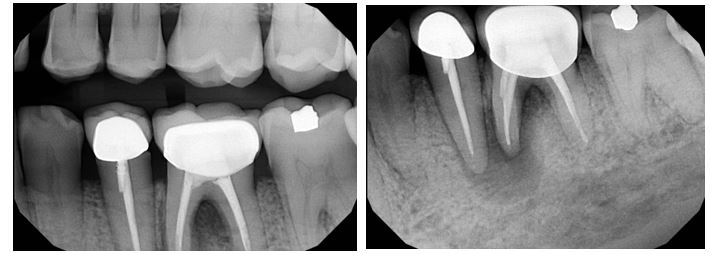

Radiographic evaluation: Periapical and bitewing radiographs of the mandibular left posterior quadrant show existing PFM crowns and prior root canal therapy on teeth #20 and #19, with a small, nonretentive post on #20. A large periapical radiolucency is noted at the M root of #19 which is confluent with a secondary large radiolucency at #20. The radiolucency on the M root of #19 extends towards the furcation.

A limited FOV CBCT was exposed revealing an area of low density encompassing the root apices of #19 and #20. There was no evidence of missed/non-negotiated secondary anatomy. Existing root fills are greater than 0.5mm from the radiographic apex. The areas of reduced radiographic density are consistent with the appearance of apical periodontitis, and are not in close proximity to the inferior alveolar nerve.

Clinical evaluation: Probing depths ranged between 2-3mm in the mandibular left posterior quadrant save for the MB of tooth #19 where a probing depth of 10mm was noted. Sinus tract on the attached gingiva buccal to #19 was noted. Teeth #20 and #19 have class 1 mobility. Both PFM crowns on #19 and #20 present with clinically intact margins.

Treatment Rendered: Sometimes we have the opportunity to combine multiple treatment strategies in complex cases. In this case, non-surgical retreatment of #8 was performed in tandem with decompression. After discussing his treatment plan with the referring GD, the patient was seen first by his GD for removal of the existing crown and placement of a long-term milled temporary crown. The patient then returned to our office for the post and gutta-percha removal with placement of intracanal calcium hydroxide. This was followed by immediate decompression of the lesion. The decompression technique used was the simultaneous needle aspiration and irrigation method described by Hoen et al. (JOE, 1990). This involves placement of two 16 gauge needles into the lesion with simultaneous aspiration and irrigation with saline (no long-term drain was used). 30ml of saline was used to irrigate the lesion until the aspirated fluid was clear.

After one month, the patient returned for follow-up and the buccal sinus was still present. The tooth was re-accessed and the calcium hydroxide was replaced. At the two month mark, the buccal sinus tract was healed, but the canal still had continued mild drainage internally. A third round of calcium hydroxide was applied and left in place for 3 months. When the patient returned (5 months after initiating treatment), evidence of healing was observed radiographically around #7 and #8. RCT #8 was completed with an MTA obturation and RMGI orifice barrier. Sufficient ferrule and peripheral tooth structure was present and another post was considered not necessary.

After 2 months of calcium hydroxide. Early evidence of periapical healing, The buccal sinus tract healed but the canal was still draining internally. PA taken immediately after third round of calcium hydroxide (powder) applied.

Immediate Post-op (after long-term CaOH for 5 months)

6-month recall: Tooth #8 was asymptomatic and with no buccal sinus tract present. Tooth #7 remains responsive to cold testing. The patient had not returned to their GD for the permanent crown. The mobility in #8 was notably reduced and significant healing was observed radiographically. The lesion may heal with an apical scar, but apical surgery will likely not be necessary. The patient was scheduled for a 12-month recall and advised to return to their GD soon for the permanent crown.